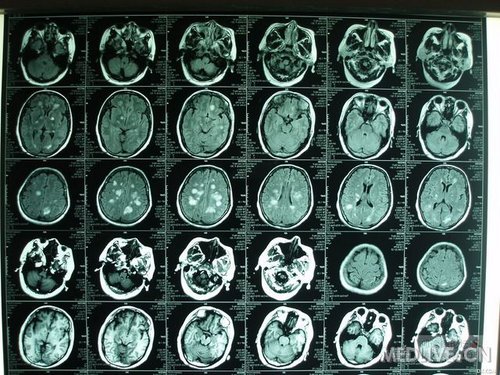

1多发性腔隙性脑梗塞多发性腔隙性脑梗塞多发性腔隙性脑梗塞多发性腔隙性脑梗塞((((脑白质病脑白质病脑白质病脑白质病))))腔隙性脑梗塞是在高血压腔隙性脑梗塞是在高血

脑白质病诊治:边答题,边学习_脑白质病_多发性